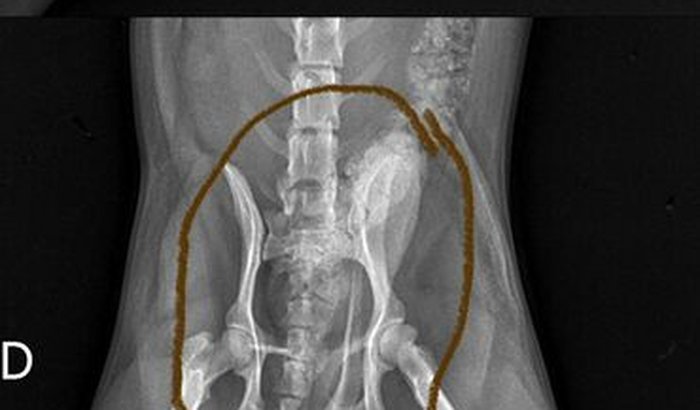

Ola, sou o Naylon, no dia 03/07/2023 eu resolvi sair para rua sem a supervisão dos meus pais e fui atropelado por uma motocicleta e quebrei a minha perna esquerda, meus papais estão me levando ao veterinário para eu fazer exames, porém, dentro desse alguns exames foi recomendado a fazer uma cirurgia urgente na minha patinha esquerda é tem um Ossinho que está preste a perfura minha Bixiga 😔por isso peço ajuda de cada um que estiver lendo. E quem puder me ajudar com qualquer valor ou compartilhando já me ajudaria muito. Desde já agradeço, um abraCÃO do Naylon. ❤️🐶